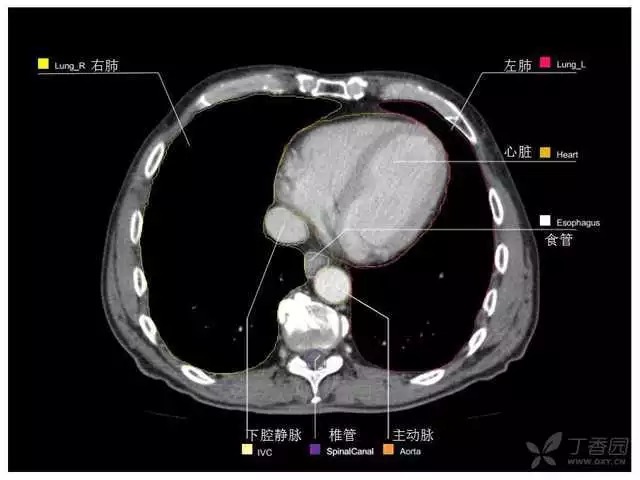

腹部肝脏高清CT断层的图谱

全腹部高清CT图谱,淋巴结彩色图谱,血管解剖图谱大汇总!